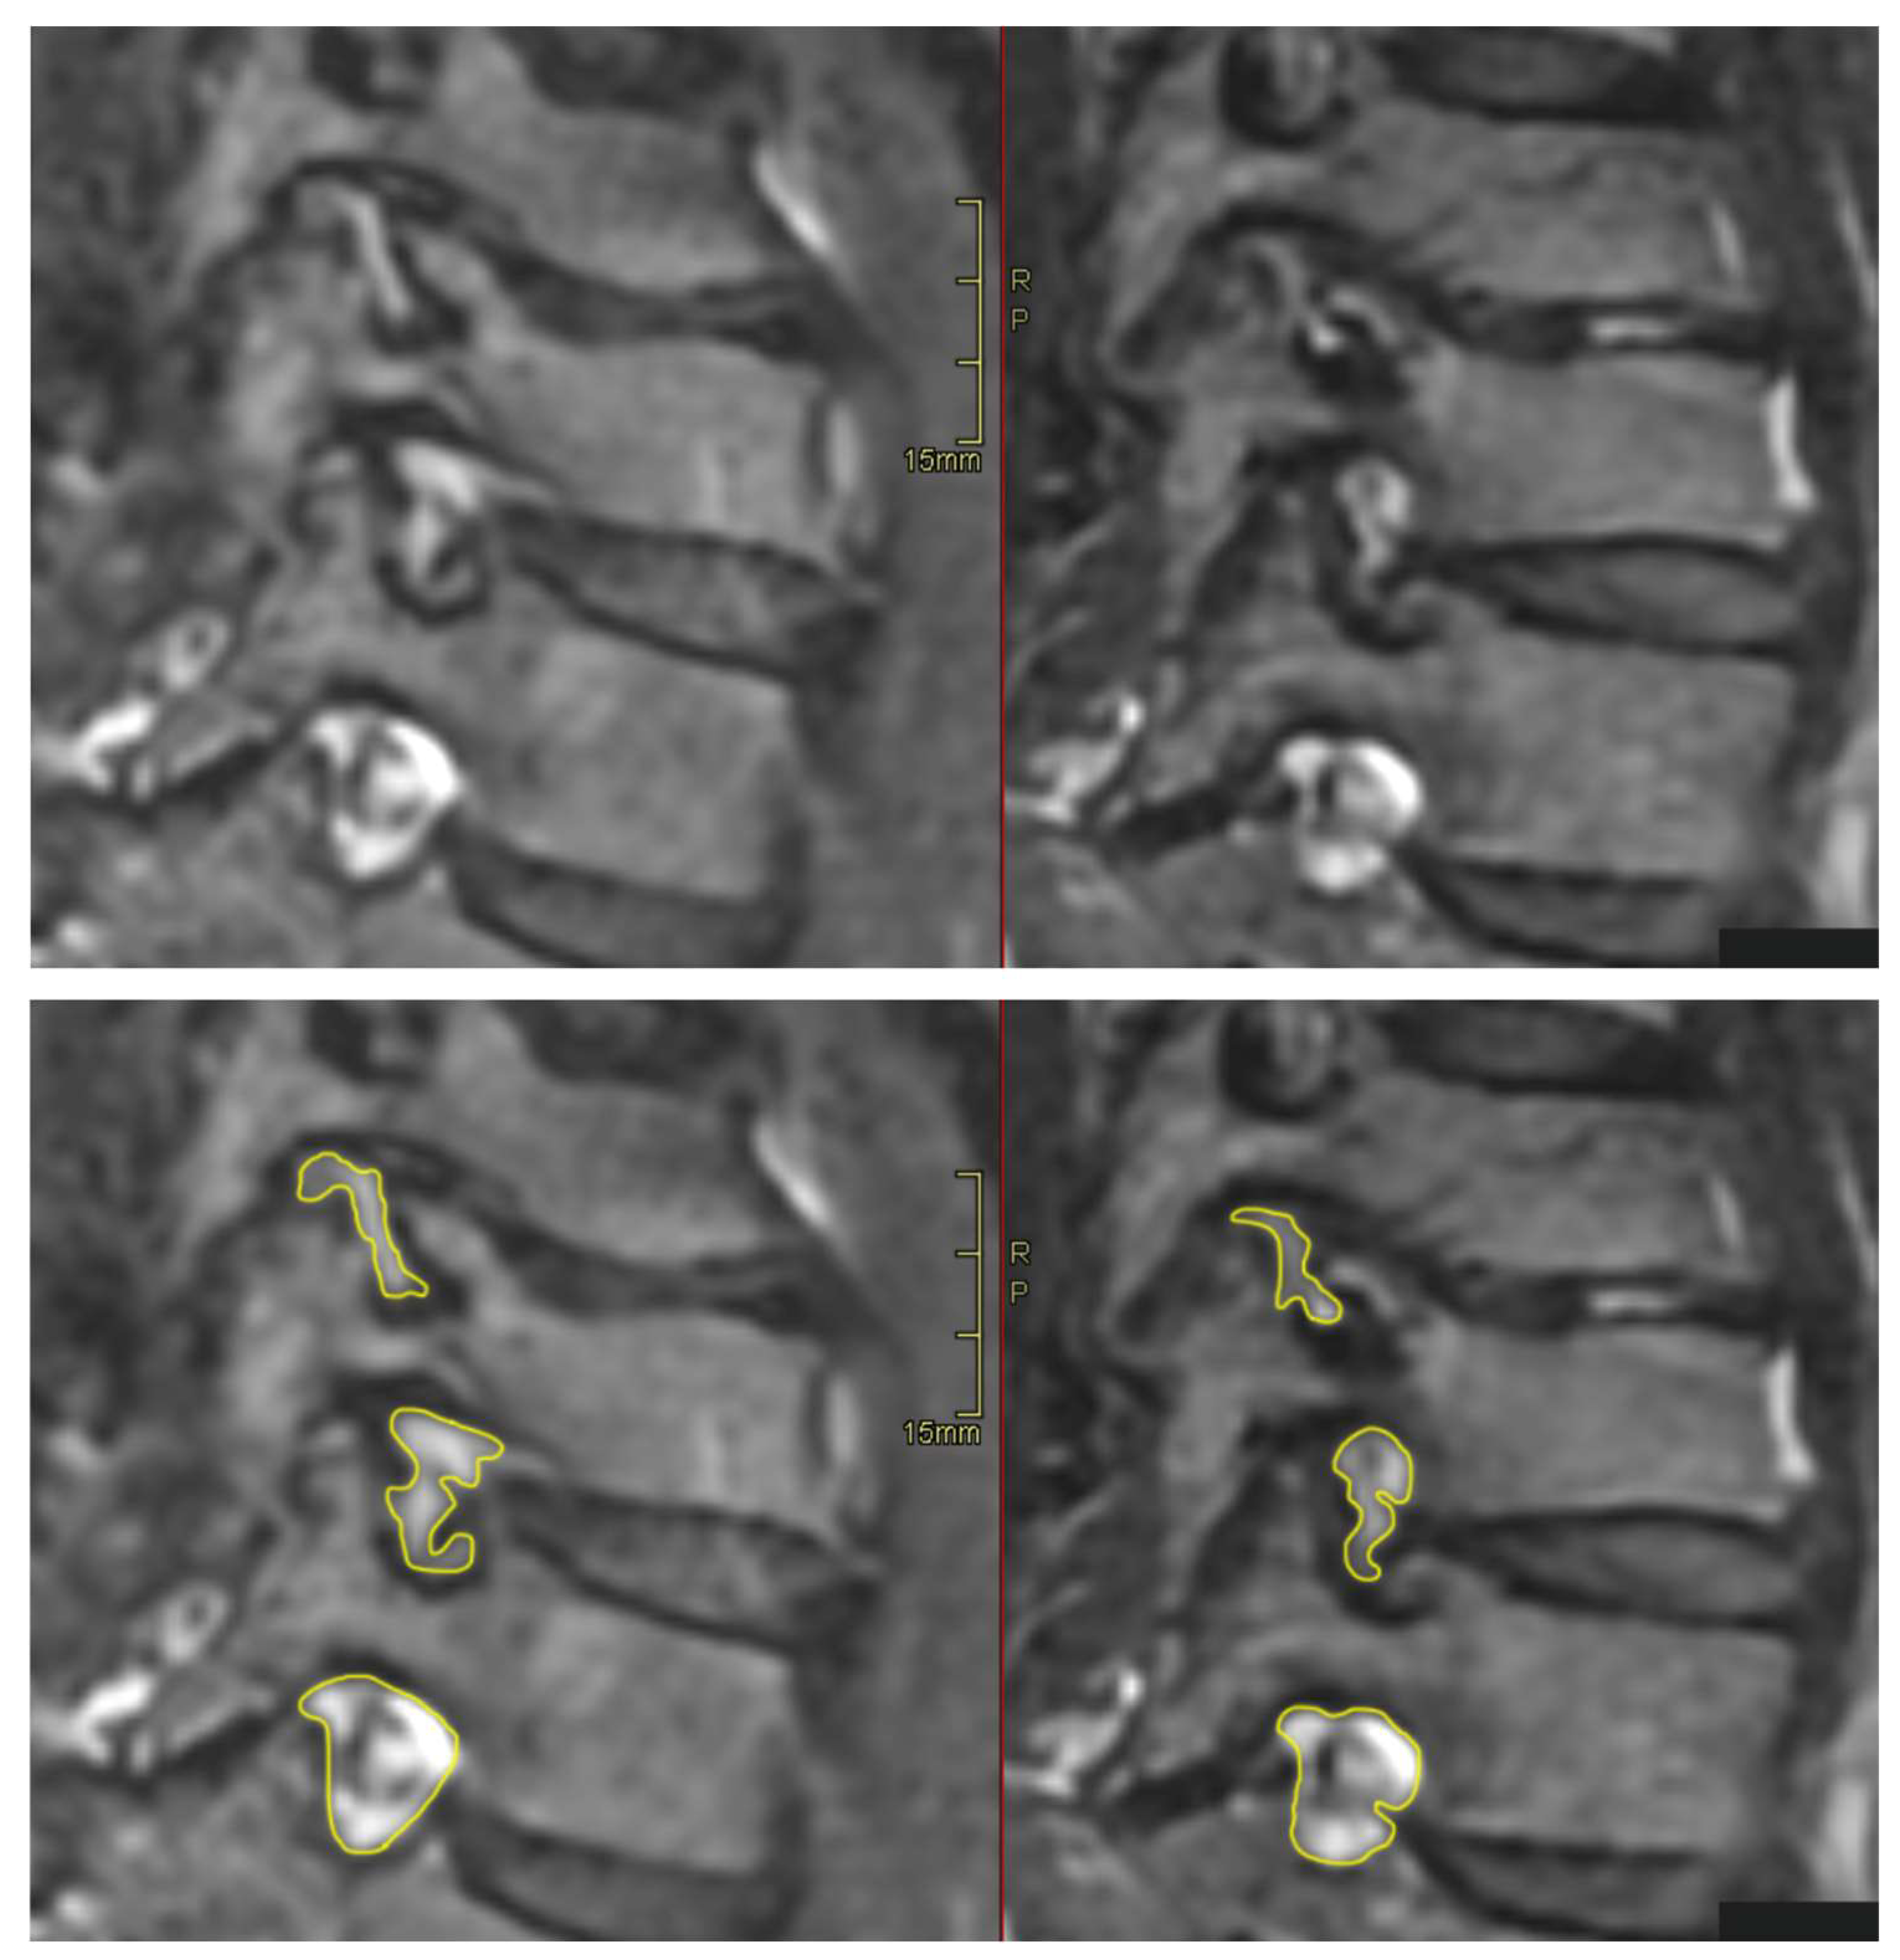

All patients were positioned without any complaints in the DMRICS apparatus, outside the MRI gantry. The patients were subsequently positioned within the MRI for a relaxed image acquisition. After successfully conducting the simulated Spurling test, immediate imaging was performed, which produced clinically acceptable image quality in 9 out of 10 patients in both relaxed and provoked positions, as shown in Figure 2 and Figure 3.

3.5. Qualitative Grading of Foramina in Relaxed and Provoked Positions

Significant changes in the gradings of Park and Kim classifications, respectively, after provocation (both p = 0.000) were seen. After applying the simulated Spurling test, all initially labeled stenotic foramina were classified as Park grade 2 or 3, with some moving up by 1 grade and others by 2 grades. A total of 13 out of 27 gradings by Park and 9 out of 27 gradings by Kim escalated to a higher grade after provocation. However, there were no significant alterations in the quantitative assessments. In foramina with high Park gradings (2 or 3) in the relaxed images, only minor area changes were observed, depicting that the degenerative segments are less dynamic, as seen in Figure 4.

In accordance with the foraminal changes related to Park gradings during provocation, the foraminal Kim gradings during provocation were all assessed as grade 2, compared with 1 or 2 in the relaxed position, as seen in Figure 5.

The significant increase in the qualitative gradings of the foramina when comparing MRI before and during the simulated Spurling test indicates that a Spurling test leads to higher Park and Kim grades. This offers not only insights into the variations of the often-employed clinical Spurling test but also suggests a possible clinical utility for dynamic MRI. The method could help in determining the severity of foraminal stenosis and identifying the impacted nerve roots if they are not distinctly discernible in a routine, relaxed MRI, especially when several foramina are narrow on a routine MRI and the symptoms and clinical examination cannot discriminate which nerve root(s) are giving rise to the experienced pain. However, for the foraminal area and cross-distance measures, no significant changes were detected in the present work. The reason for these contradictory findings may be that the foraminal shape shifts with compression and thereby the nerve compression may increase, even if the overall area is not changed or even increases; see Figure 2 and Figure 3. Further, the magnitude of measurement error in such small structures, especially for the axial-cross-distance measurements may also play a role here.

Figure 2. The upper (left) image depicts an oblique image in a relaxed position compared with the (right) image taken during the Spurling test. The foraminal areas are marked in the lower pair of images.